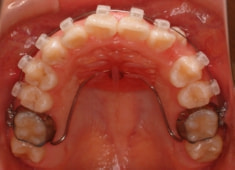

治療開始時

治療開始から5ヶ月後